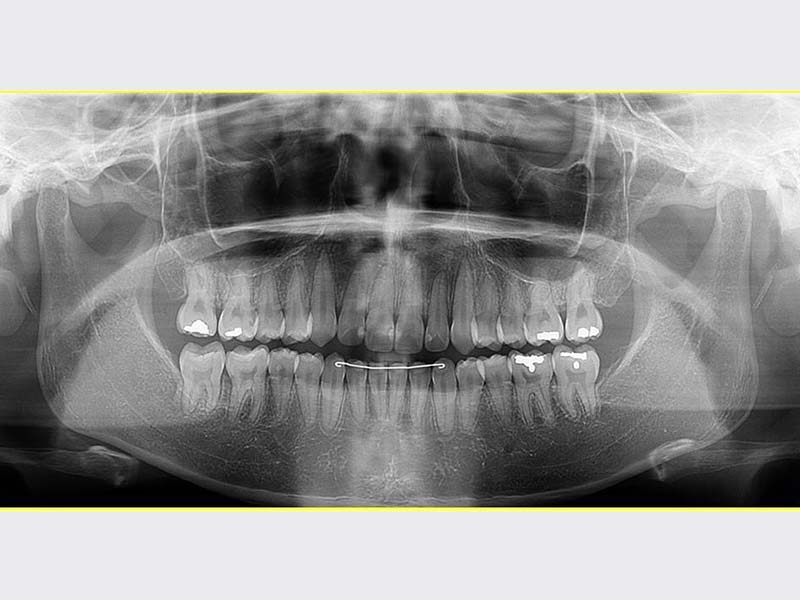

智齒手術

• 智齒手術